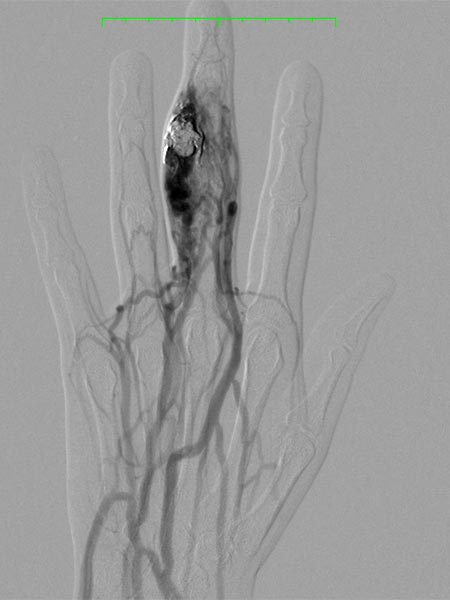

Das Rezidiv der AVM hier in der vergrößerten Zielaufnahme des D III während der Angiographie mit deutlicher Vergrößerung im Vergleich zu den alten Angiographien (nicht abgebildet). Die DSA-Aufnahmen nach transarterieller antegrader Punktion der Arteria brachialis zeigen eine hypervaskularisierte AVM von Fingermittel und -endglied.

Angiographische Abschlußkontrolle mittels Katheterangiographie der rechten Hand von transarteriell über die Arteria ulnaris. Komplette Devaskularisation des AVM Nidus, keine Fast-flow-Shunts mehr angiographisch abzugrenzen. Der Befund ist damit resektionsfähig.